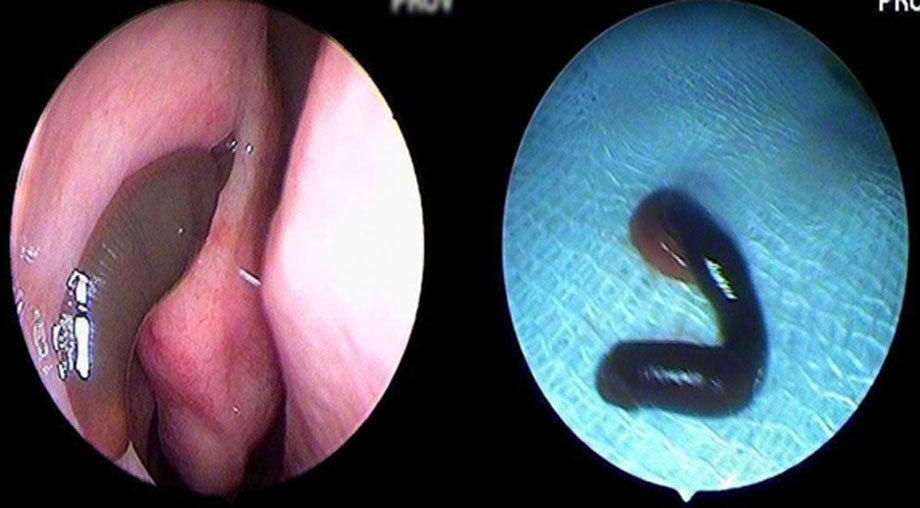

Trước đó, bệnh nhân vào viện tình trạng thường xuyên chảy máu cam từ mũi trái, số lượng ít và tự cầm máu; không có ngạt mũi, không chảy nước mũi. Gia đình cho biết, cách đây gần 1 tháng bệnh nhân có đi rừng chặt củi và rửa mặt ở khe suối. Bệnh nhân được tiến hành kiểm tra nội soi mũi và phát hiện thấy một con vắt trong hốc mũi bên trái, dài khoảng 3cm, che kín khe mũi giữa và khe mũi trên.

Trước đó, các bác sĩ Khoa Tai – Mũi – Họng của Bệnh viện A Thái Nguyên đã nhiều lần thực hiện nội soi gắp thành công con vắt cho các bệnh nhân trong tỉnh.